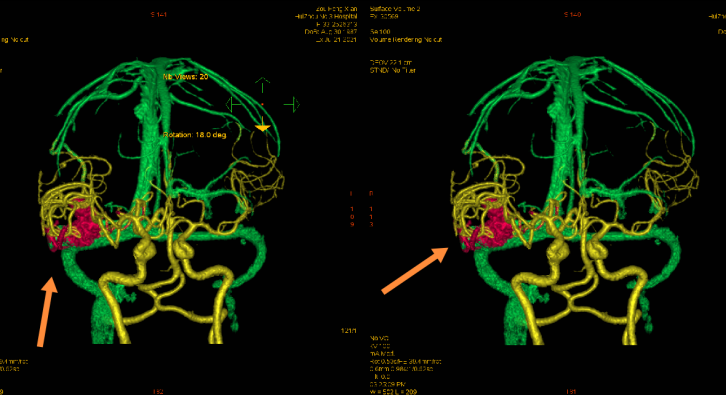

介入栓塞前、后血管造影